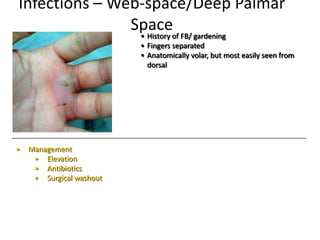

- Conditions that require emergency referral are discussed, such as bleeding, amputation, replantation, compartment syndrome, infections, and high pressure injection injuries. Proper management of these conditions focuses on rapid assessment and treatment to prevent further tissue damage.